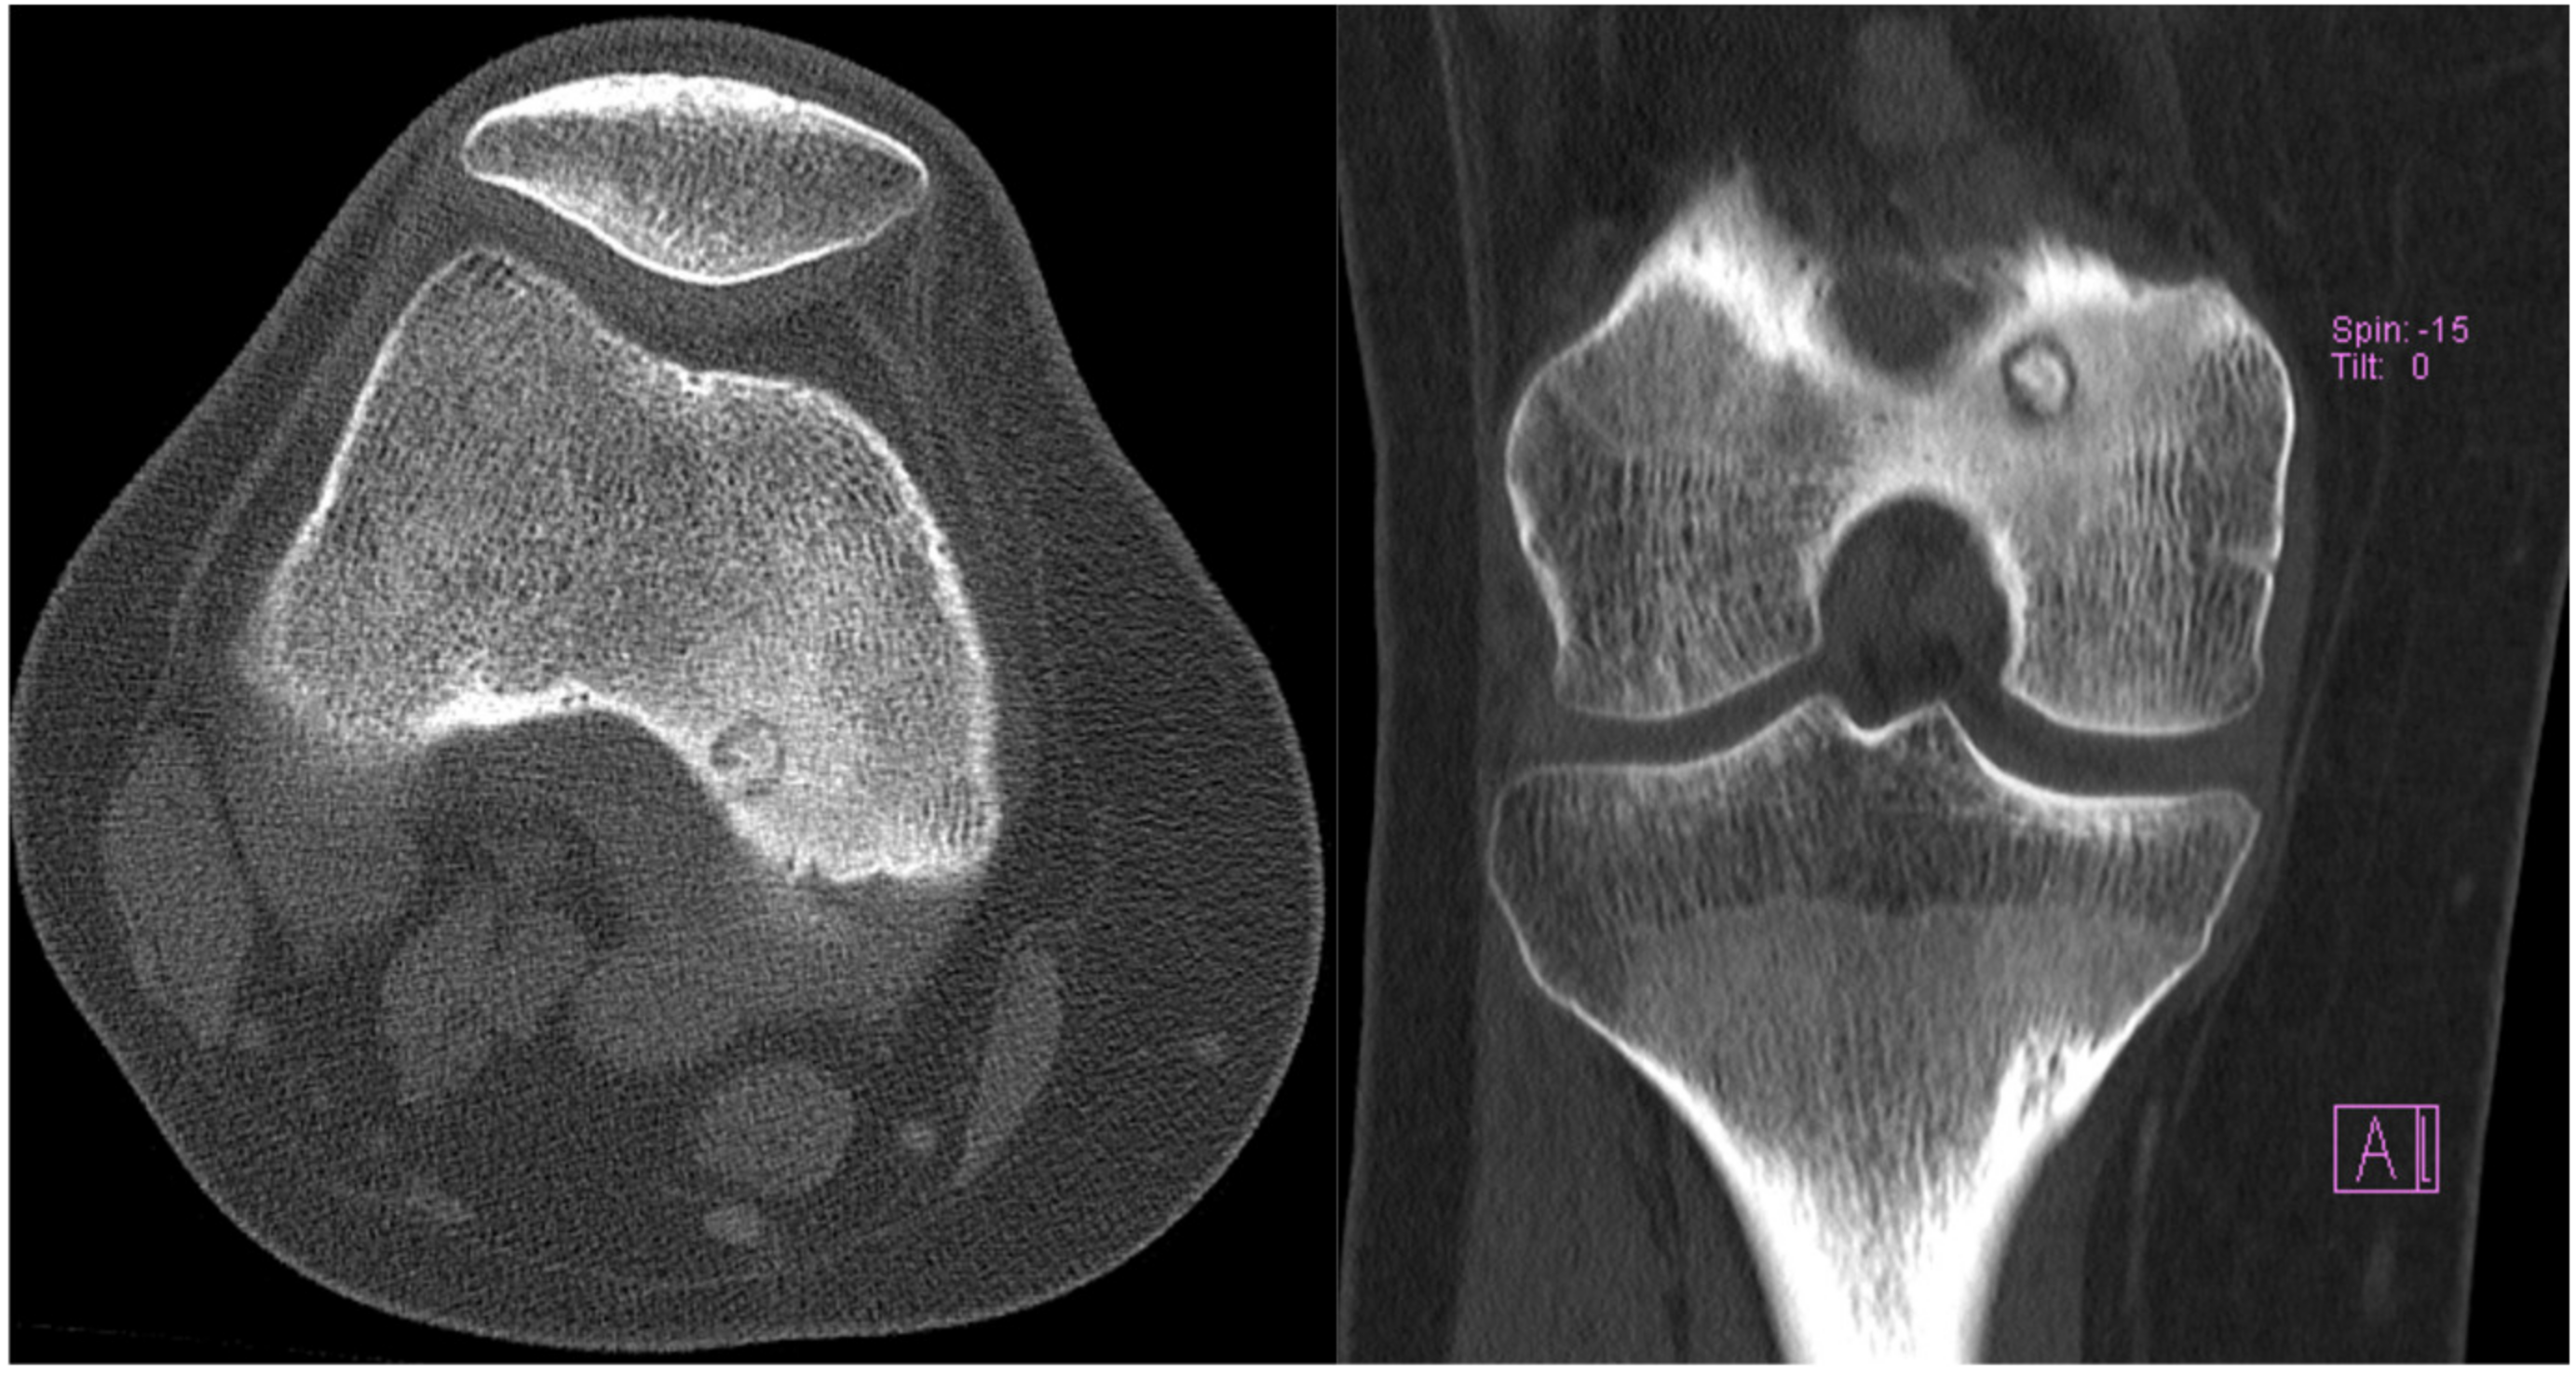

2. Case 1